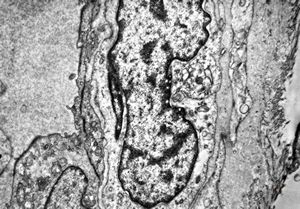

brain vessel - CADASIL - arrows:granular osmiophilic material (GOM)between basement membranes

brain vessel - CADASIL - arrow:granular osmiophilic material (GOM)in basement membrane